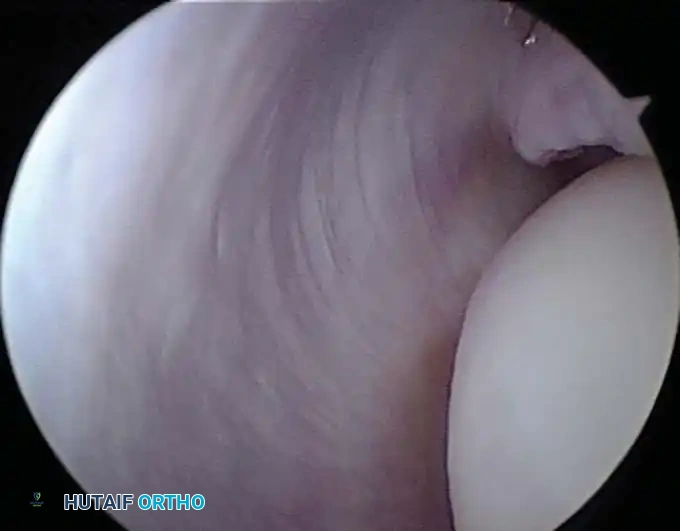

Posterior Portals

Posterior portals are essential for evaluating the olecranon fossa, the posterior trochlea, and the triceps insertion.

- Direct Posterior Portal: Located 3 cm proximal to the tip of the olecranon, directly in the midline. It traverses the triceps tendon.

- Posterolateral Portal: Located 2 to 3 cm proximal to the olecranon tip, just lateral to the lateral border of the triceps.

These portals are relatively safe, provided the ulnar nerve has not been previously transposed and the instruments are directed accurately into the olecranon fossa.